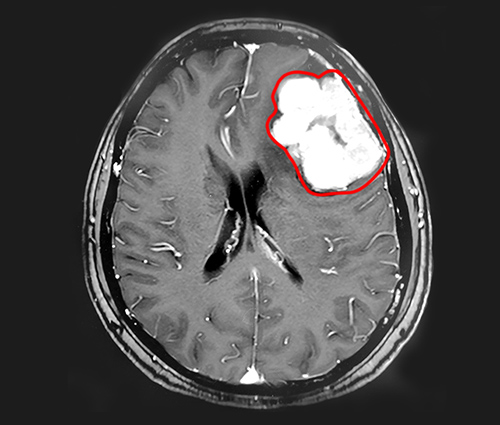

▲MRI影像显示,患者左侧额叶有体积较大的肿瘤

巨大脑膜瘤被顺利切除

在蓝十字,程阿姨的头颅核磁共振影像显示,患者左侧额叶有巨大团块状异常信号,大小约5.5*4.3*4.8cm,临近的左侧侧脑室受压变窄。在这个肿瘤周围,还有多枚体积较小的肿瘤,具有脑膜瘤的典型特征。